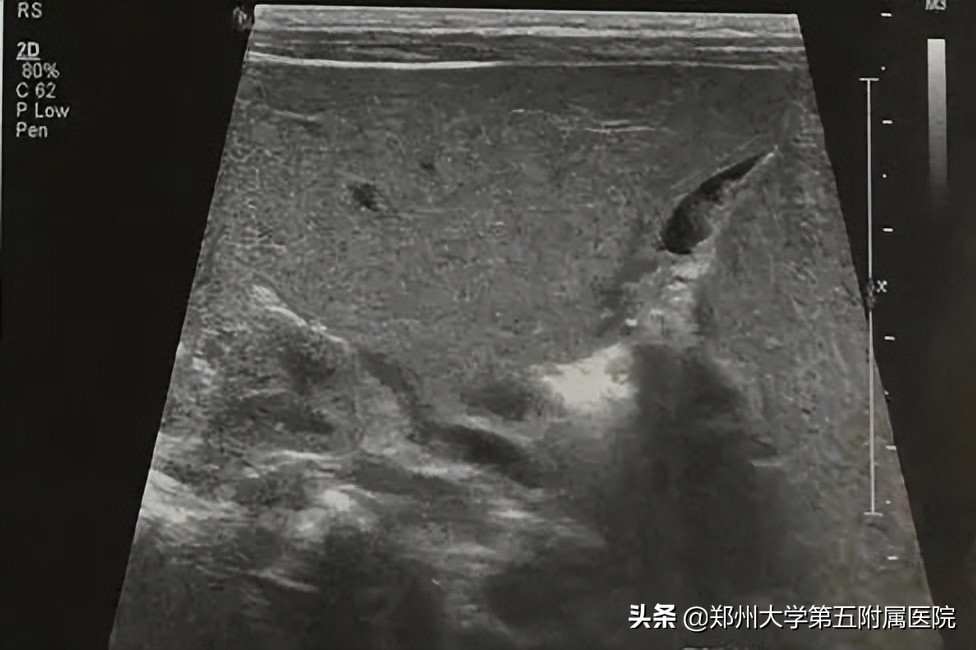

婴儿肝炎综合征(简称“婴肝”) ,因新生儿期或婴儿期病毒感染造成,为生理性黄疸消退后又出现黄疸,或持续性黄疸进行性加重,大便一般为黄色。超声表现为肝大、肝脏实质回声正常或增强,胆囊充盈良好或充盈较差,但 胆囊形态大多流畅、自然 (图1)。 喂奶后 1.5-2小时复查,充盈较好的 胆囊会有不同程度的收缩 ,充盈差或萎瘪的胆囊会有少量的充盈。多数情况下,患儿的肝外胆道发育正常;重症肝炎时胆囊充盈差或不充盈,形态僵硬,喂奶前后无变化,这时与胆道闭锁鉴别困难,需要结合病史 短期内(1-2周)复查 ,而且经过治疗后,黄疸程度不断减轻至恢复正常。

▲ 图1